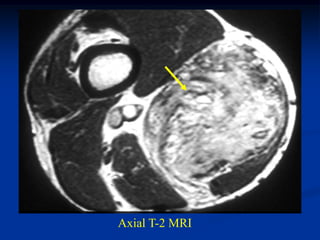

Case #1185

59 year female with

intramuscular lipoma

anterior proximal thigh

Coronal T-1 MRI

Axial T-2 MRI

at lower level

Fat subtraction MRI

showing signal void

in lipoma

Case #1185 59 yearfemale with intramuscular lipoma anterior proximal thigh Coronal T-1 MRI

• 54.

• 55.

Axial T-2 MRI atlower level

• 56.

Fat subtraction MRI showingsignal void in lipoma